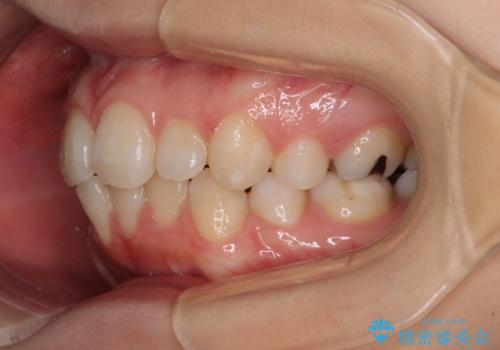

- 下顎前歯を中心に、以前行った矯正治療の後戻りが気になるとのことで来院された患者様です。

後戻りは軽度であったため、インビザライン・ライトにて治療を行うこととしました。